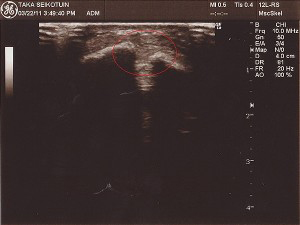

超音波画像診断検査

超音波を用いた画像解析装置で、分かりやすく言いますとエコー検査です。

骨、靭帯、筋肉、関節、腱、軟骨、関節包、血流、滑膜、末梢神経を診ることができます。

レントゲンには映りにくい小さな骨折や肋骨骨折、関節水腫、血腫、早期の疲労骨折、シンスプリント等がわかります。

また、骨折部や筋膜傷部の癒合や、血腫を確認し、固定材や包帯の除去の判断、施術計画の作成に有効です。